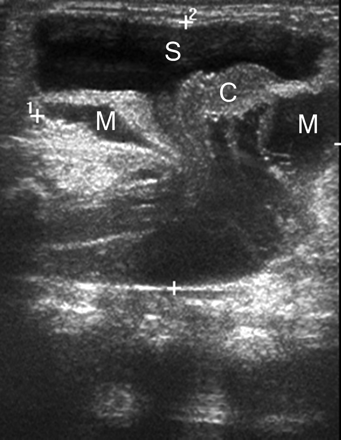

一个已经男孩看到一个突出的无痛性软质量(8×7厘米)在出生后骶区,与完整的皮肤覆盖。超声显示囊性扩张的远端中央管周围扩张蛛网膜下腔(图1)。MRI证实的诊断终端脊髓囊肿状突出的典型发现trumpetlike扩口syringocele和脑脊髓膜突出(图2)。

图2

核磁共振成像

轴向t1 (A)和t2加权磁共振扫描显示类似的描述(B)作为超声。箭头指向变形和流离失所的脊髓。M =脑脊髓膜突出;S = syringocele;Vb =椎体。